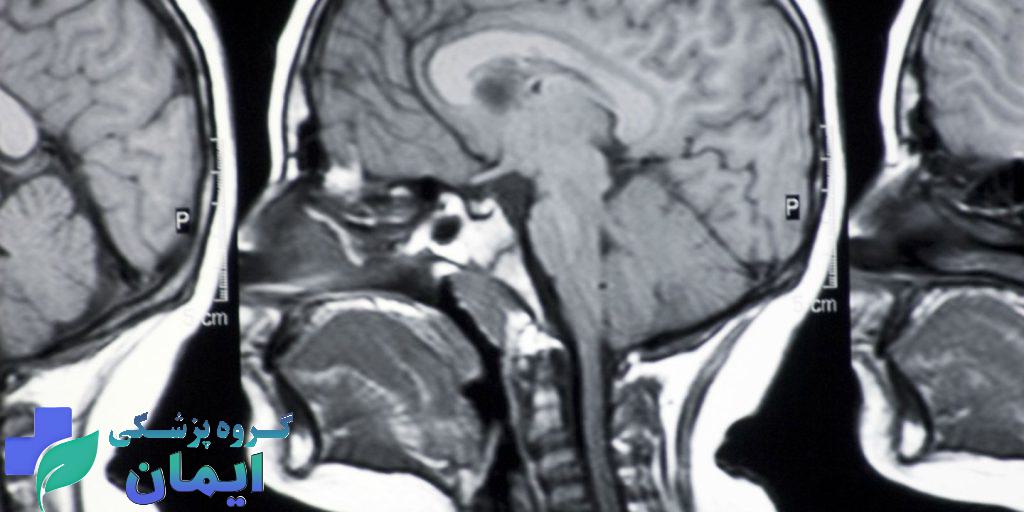

در حال حاضر، ام آر آی (MRI) دقیقترین و قابلاعتمادترین روش تصویربرداری برای شناسایی ضایعات ناشی از ام اس در مغز و نخاع است. با استفاده از ام آر آی، میتوان ضایعات دمیلینهشده (نواحی آسیبدیده میلین) را بهوضوح مشاهده کرد و روند بیماری را نیز در طول زمان پیگیری نمود. این روش همچنین در تشخیص افتراقی ام اس از سایر بیماریهای عصبی مانند لوپوس، واسکولیتها یا تومورها نقش کلیدی دارد.

ام آر آی بهترین و مطمئنترین راه برای شناخت بیماری ام اس است. در این روش، تصاویر دقیقی از مغز و نخاع گرفته میشود که بهوسیله آن میتوان نواحی آسیبدیده از جمله مناطق دمیلینهشده (جایی که پوشش میلین رشتههای عصبی تخریب شده) را مشاهده کرد. حتی ضایعاتی که هنوز علائم بالینی ایجاد نکردهاند، ممکن است در ام آر آی دیده شوند.

بیماری ام اس باعث تخریب غلاف میلین (پوشش محافظ سلولهای عصبی) در مغز و نخاع میشود. این تخریبها در تصاویر ام آر آی به شکل لکهها یا ضایعات سفیدرنگ (بهویژه در تصاویر T2 و FLAIR) دیده میشوند. پزشکان با مشاهده الگوی این ضایعات و محل آنها، میتوانند احتمال ام اس را بررسی کرده و تشخیص دهند.

- وجود چندین ضایعه سفید در ماده سفید مغز، بهویژه در اطراف بطنها، مخچه و نخاع

- ضایعات فعال که با تزریق ماده حاجب (گادولینیوم) روشنتر میشوند

- الگوی خاصی از پخش شدن ضایعات در زمان و مکان (که طبق معیار مکدانلد برای تشخیص ام اس استفاده میشود)